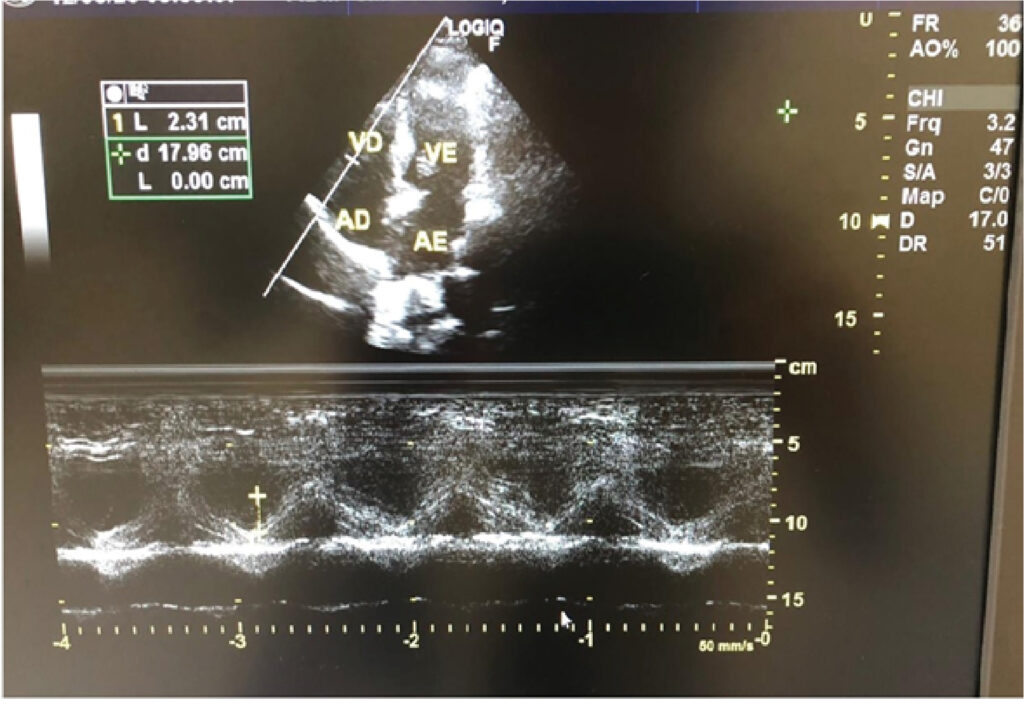

A excursão sistólica do anel tricúspide e a do anel mitral são parâmetros utilizados para se avaliar a função contrátil do ventrículo direito e do ventrículo esquerdo, respectivamente. Pouco se conhece sobre sua relação com a função diastólica ventricular esquerda.

Avaliar se os valores de excursão sistólica do anel tricúspide e do anel mitral se correlacionam com parâmetros utilizados na avaliação da função diastólica ventricular esquerda.

Estudo observacional transversal. Foram selecionados 219 indivíduos, sendo 116 mulheres, com função sistólica preservada de ambos os ventrículos. As análises foram feitas separadamente para os sexos masculino e feminino, por meio dos coeficientes de correlação de Pearson e de Sperman. Foram obtidos: excursão sistólica do anel tricúspide, excursão sistólica do anel mitral, volumes atriais e medidas relacionadas à avaliação da função diastólica do ventrículo esquerdo ao ecocardiograma transtorácico.